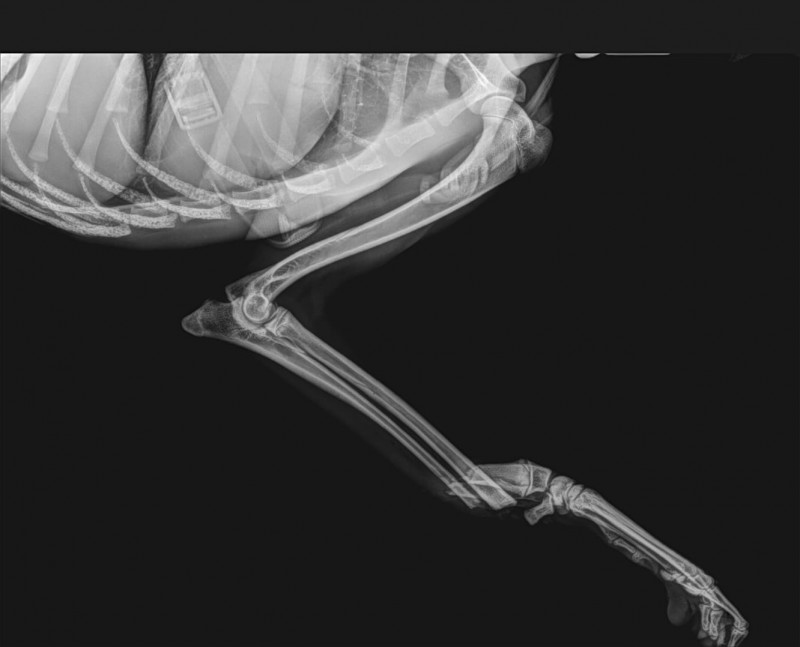

Pour Notre MERLIN, petit compte rendu des radios et du contrôle du 22.01.2025.

L'orthopédiste est très heureux du résultat car Merlin va très bien ; la consolidation des fractures est ok et la cicatrisation de la patte avant est pratiquement terminée.

Merlin peut vivre normalement sur ses 4 pattes et sans boiterie ce qui est un miracle.

Un contrôle et des radios sont prévus courant février 2025.